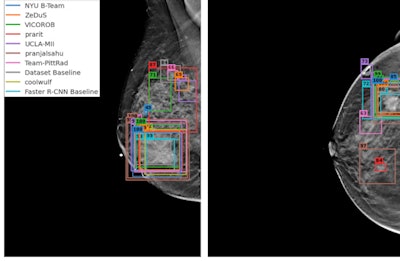

(A, B) Examples of DBT volumes containing annotated lesions that were the easiest to detect. On average, all 10 algorithms detected lesions in A and with 0.13 and 0.16 false positives, respectively. Detection bounding boxes indicate submitted algorithm predictions. The number in the upper-left corner of each box indicates the percentile of the corresponding algorithm's score with respect to the distribution of all algorithm scores for the volume. At most, two boxes per algorithm are shown, and the colors of each algorithm's boxes correspond to the free-response receiver operating characteristic curves. Images courtesy of Nicholas Konz.In the first phase of the study, teams were given 700 scans from the training set, 120 from the validation set, and 180 from the test set. The groups received the full data set in the second phase.